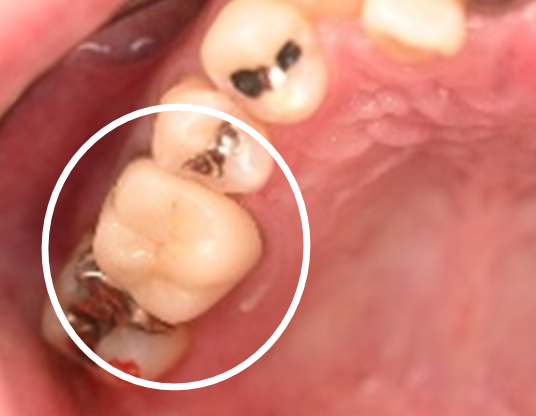

ブリッジの支台になっている奥の歯が、被せ物の中で虫歯になり、支台の役割を果たさず、前方の歯のみで支えられていました。前方の歯をそのままにして、後方の部分を切り離すと、そのまま取れてきました。中は、虫歯で歯根しか残っていない状況でした。この歯は、根管治療後、単独でオールセラミック冠を被せ、歯のないところにインプラントを埋入しました。

冠の中で大きな虫歯になり支台の役割を果たしていませんでした。

冠はブリッジを切断しただけで取れてきました。軟化象牙質を取り除いたところ、歯根しか残っていない状況で保存できるかどうかのぎりぎりのところでした。